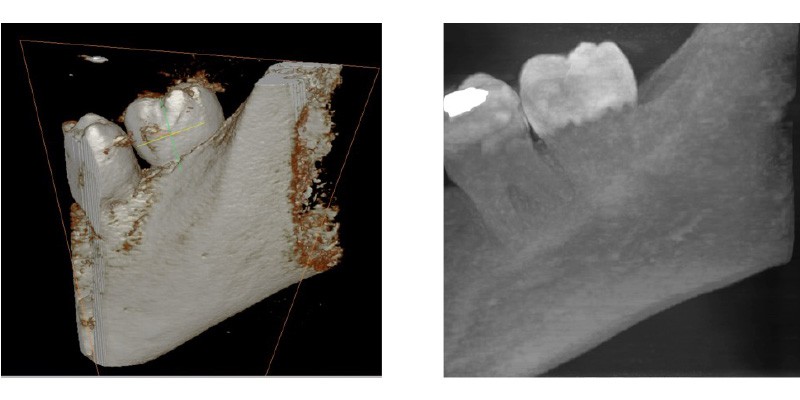

FOV 5X5 PERIAPICAL